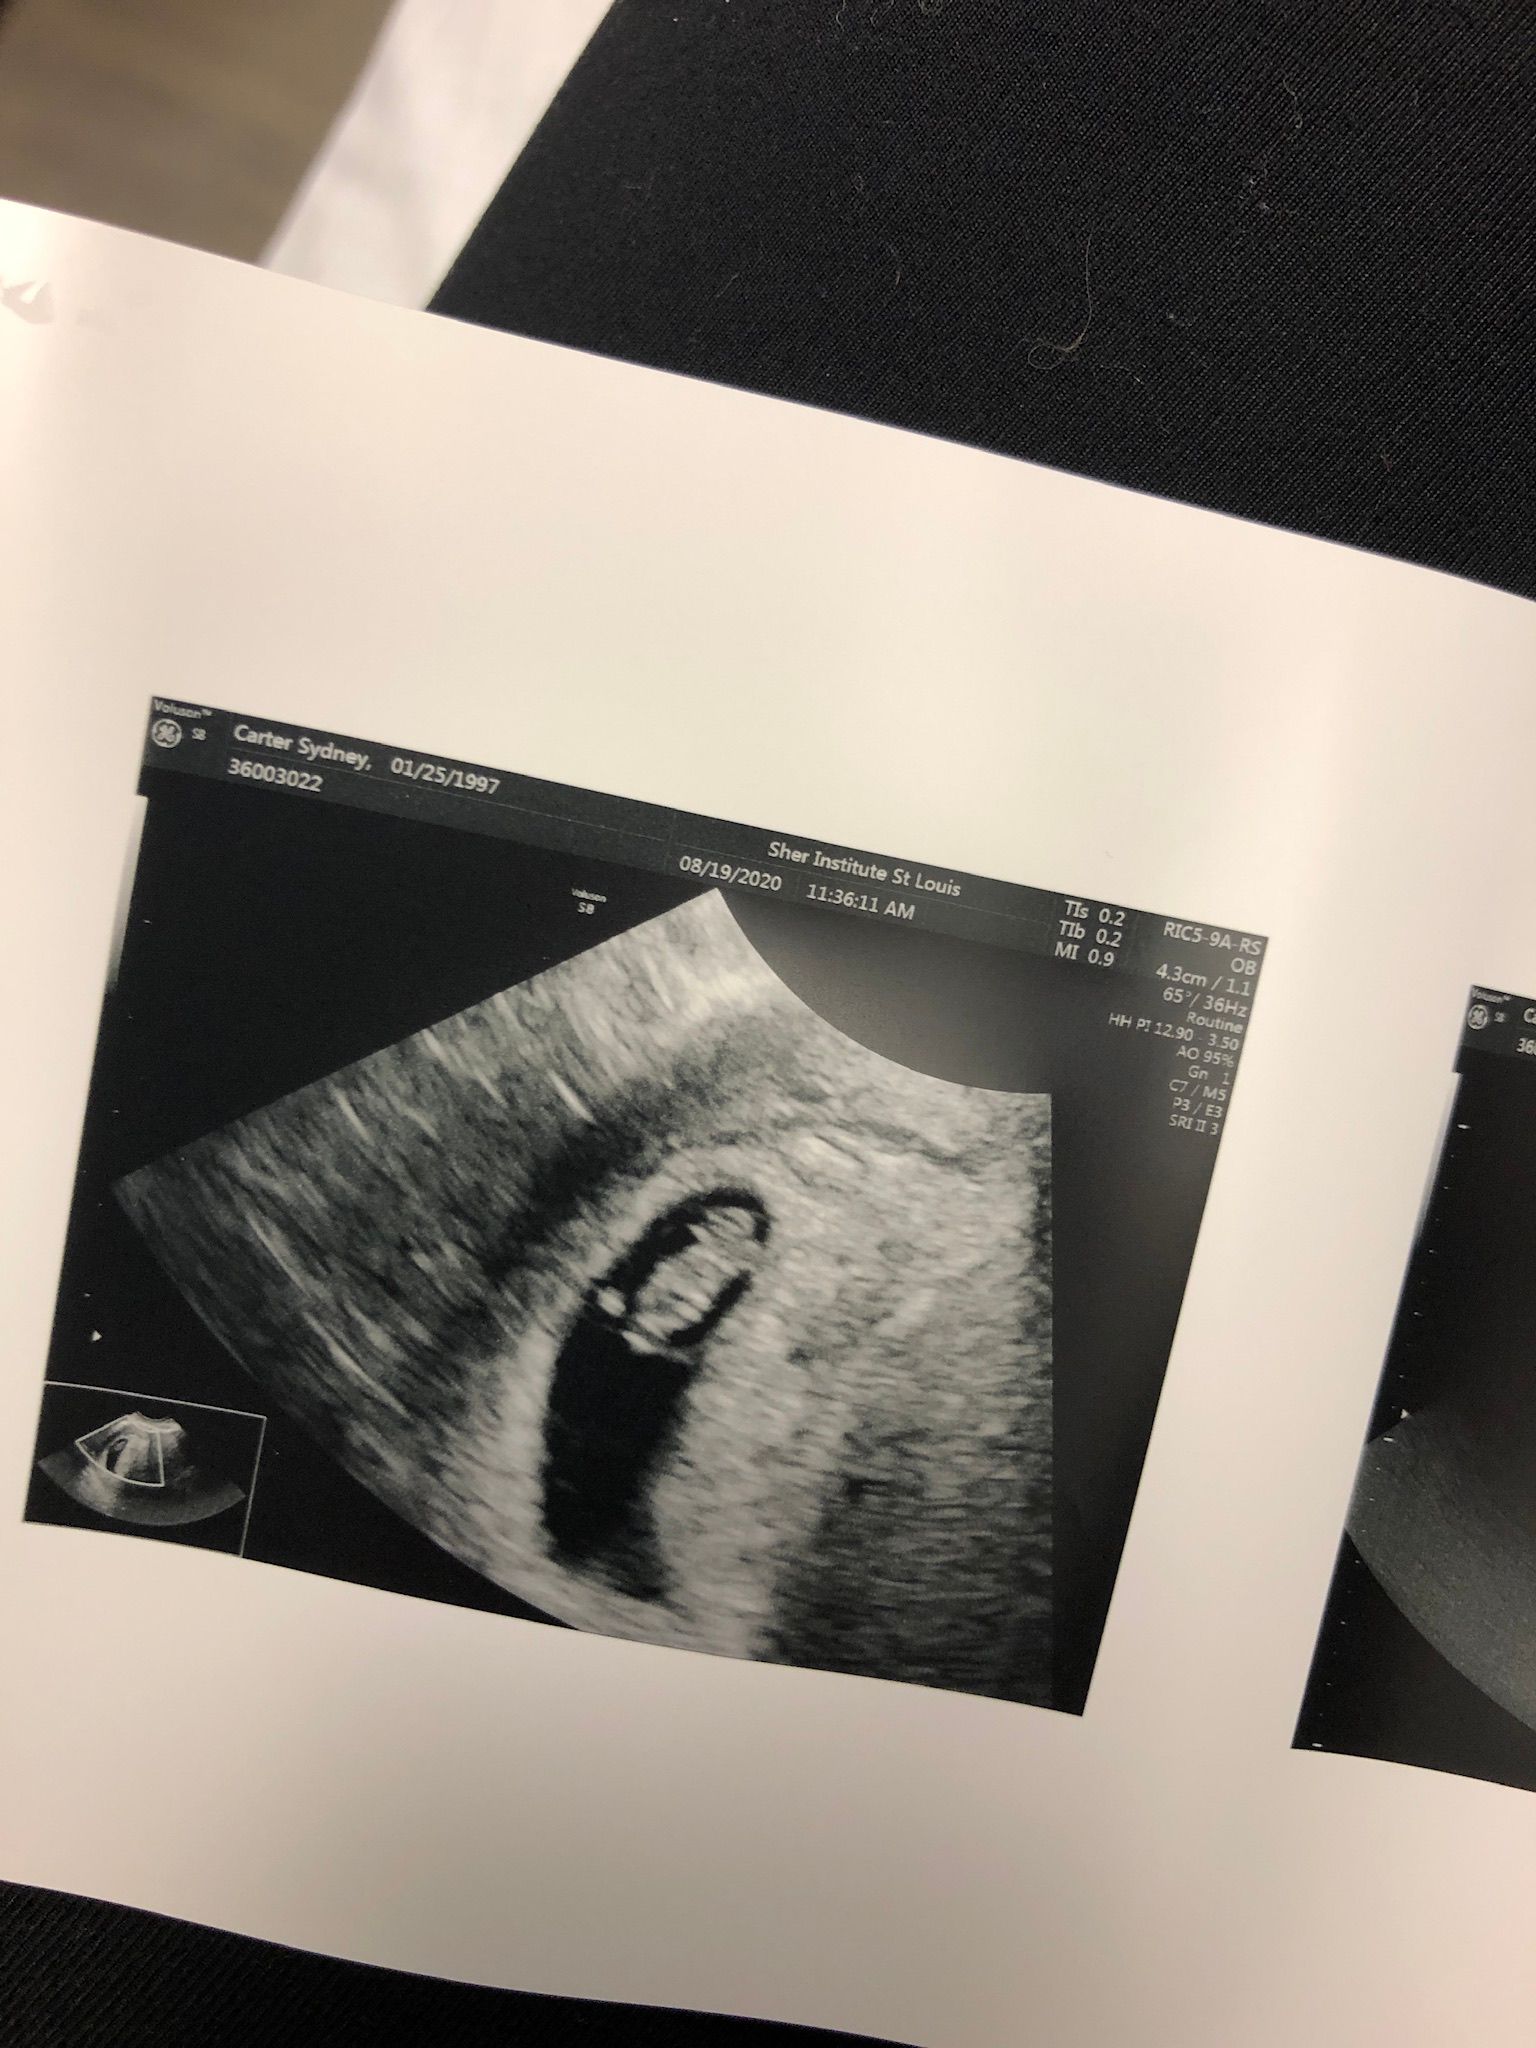

August 19: Second appointment! 7 weeks

I was so incredibly nervous about this appointment. I have felt soooo sick lately, sicker than I have ever been. So I knew that was a great sign but I was still so nervous!! As soon as she started the Ultrasound she said what a great heartbeat! Such a relief. Strong heartbeat at 144. I did intralipids and they went much quicker!! I'll be back in a week for my last appointment here.